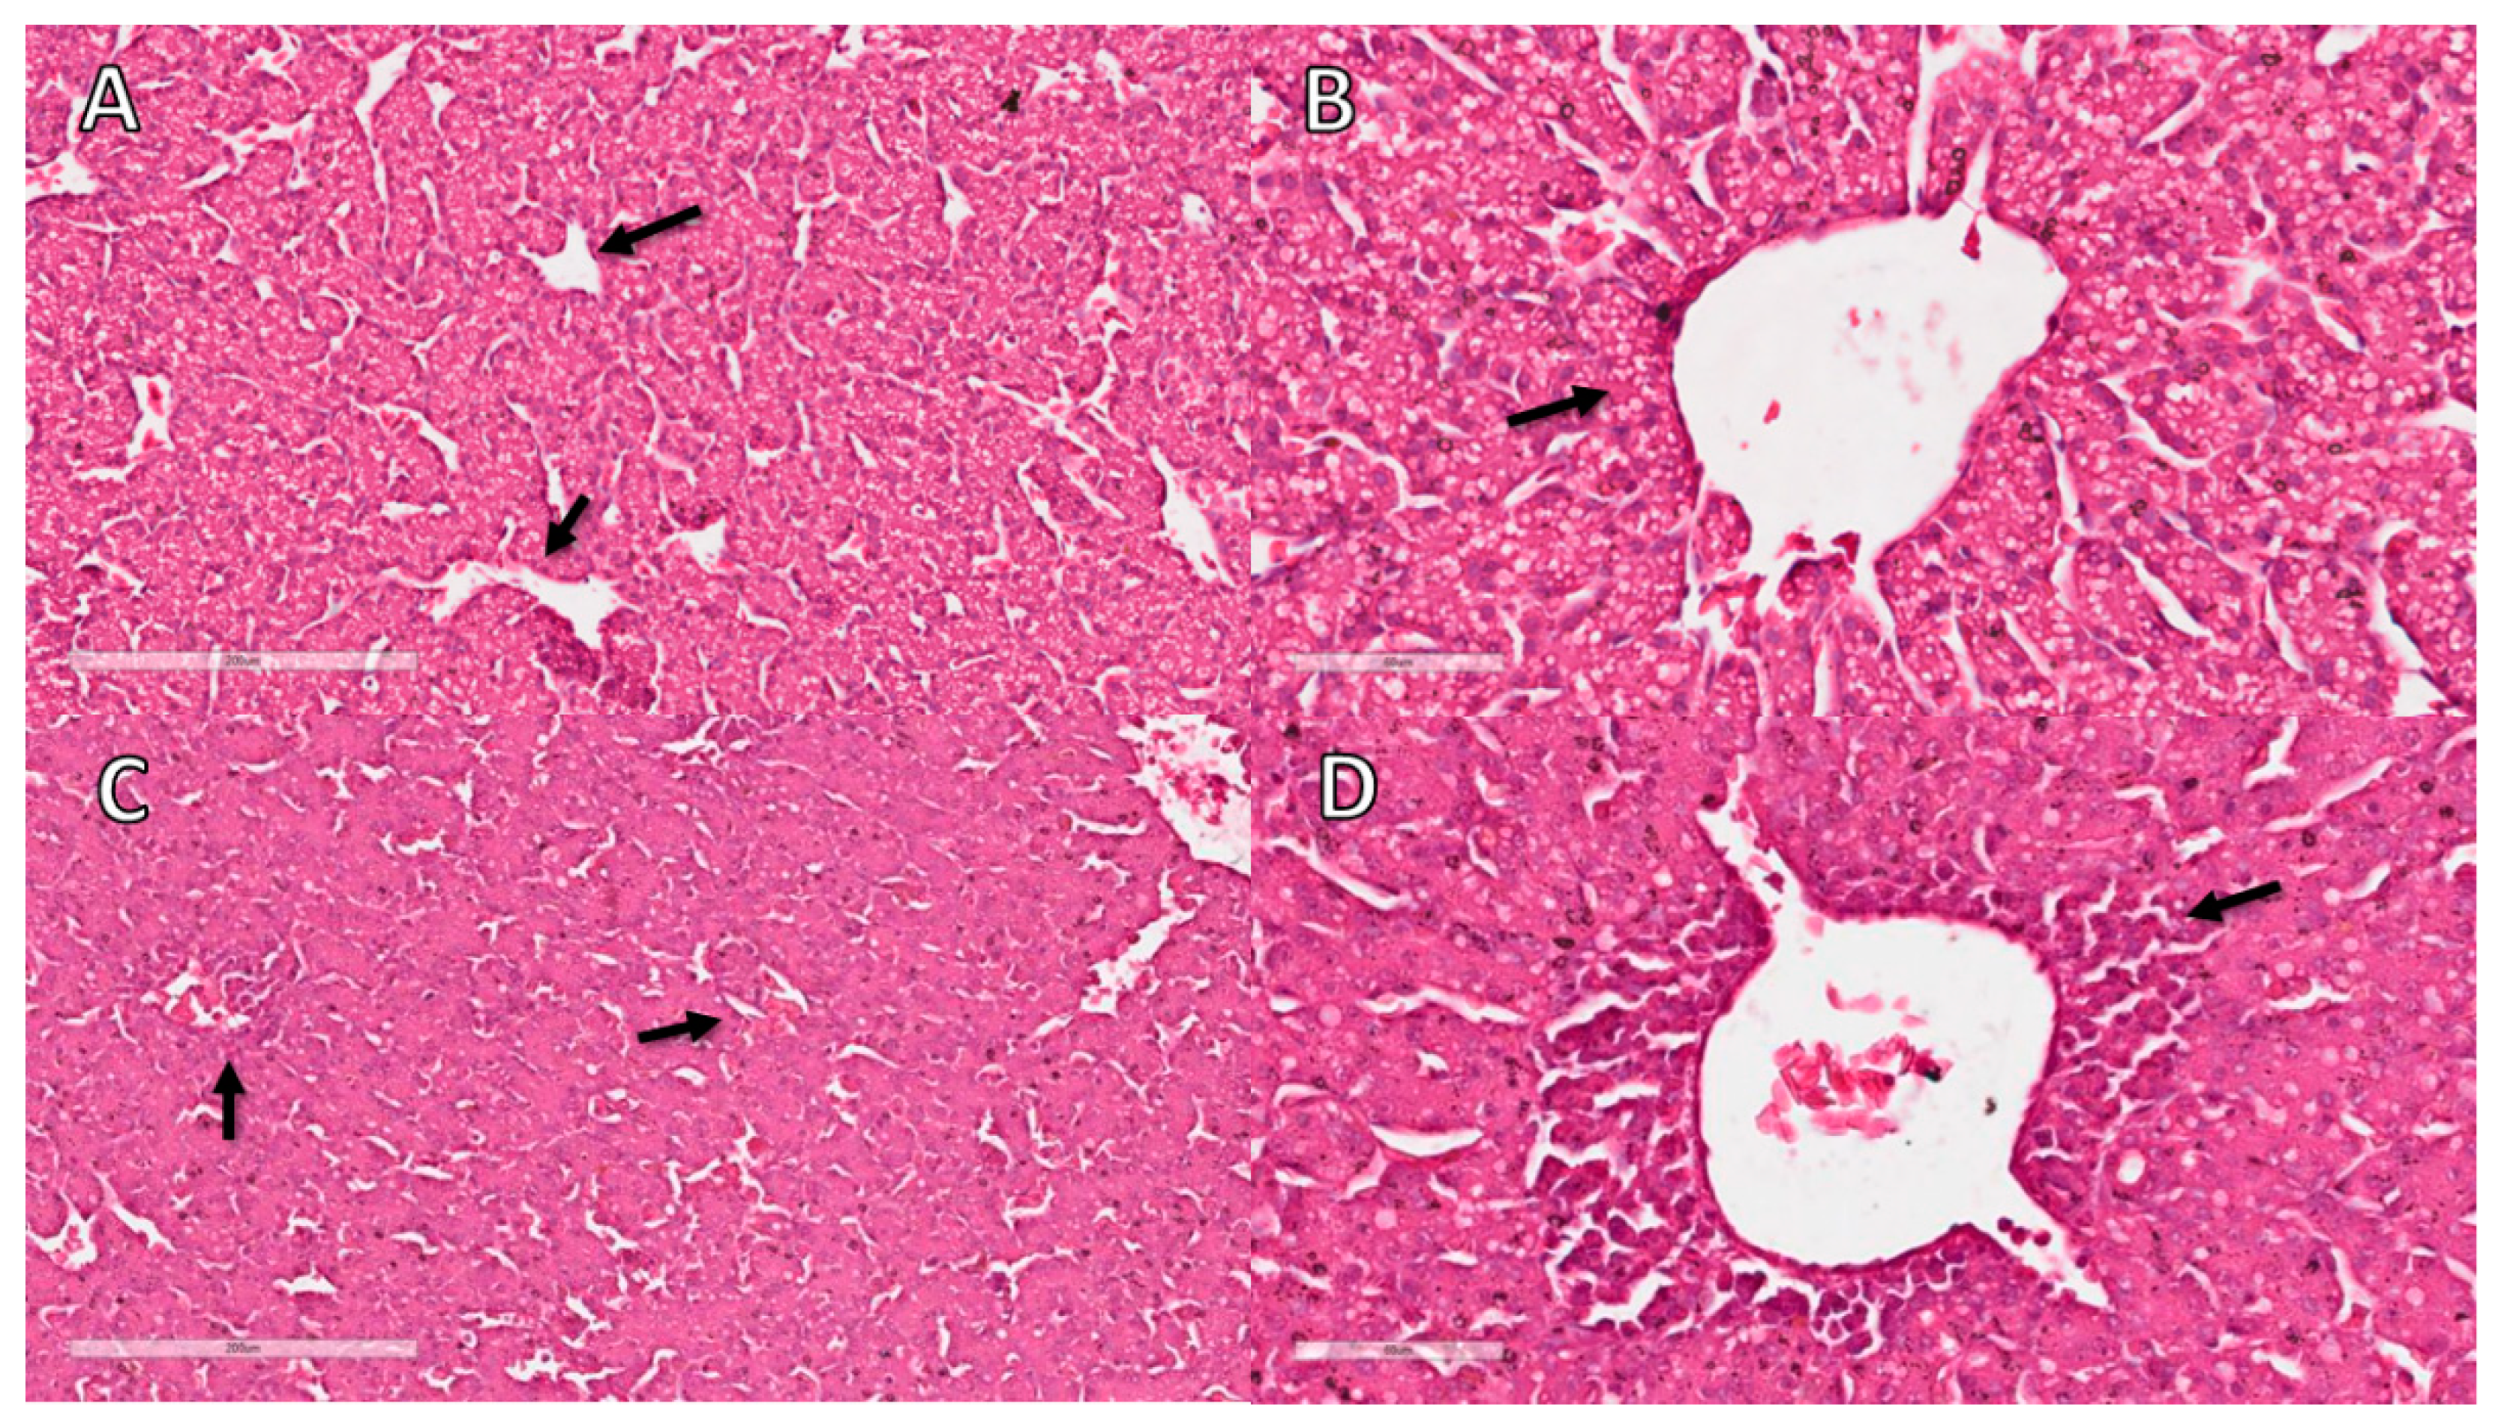

3.11. Liver Histopathological Analysis

| 10 EID | 12 EID | ||||||

|---|---|---|---|---|---|---|---|

| NC (CAM) | FG (CAM) | NC (SM) | DX (SM) | NC | FG | DX | |

| Inflammation | 0 (Mi: 0; Ma: 0) # | 1 (Mi: 0; Ma: 2) * | 0 (Mi: 0; Ma: 0) a | 0 (Mi: 0; Ma: 2) b | 0 (Mi: 0; Ma: 0) A | 0 (Mi: 0; Ma: 1) AB | 1 (Mi: 0; Ma: 2) B |

| Degeneration | 0 (Mi: 0; Ma: 0) # | 0 (Mi: 0; Ma: 0) # | 0 (Mi: 0; Ma: 0) a | 0 (Mi: 0; Ma: 3) a | 0 (Mi: 0; Ma: 0) A | 0 (Mi: 1; Ma: 1) AB | 1 (Mi: 1; Ma: 3) B |

| Necrosis | 0 (Mi: 0; Ma: 0) # | 0 (Mi: 0; Ma: 0) # | 0 (Mi: 0; Ma: 0) a | 0 (Mi: 0; Ma: 2) a | 0 (Mi: 0; Ma: 0) A | 0 (Mi: 0; Ma: 0) A | 0 (Mi: 0; Ma: 0) A |

| Circulatory change | 0 (Mi: 0; Ma: 0) # | 0 (Mi: 0; Ma: 1) # | 0 (Mi: 0; Ma: 0) a | 1 (Mi: 0; Ma: 3) b | 0 (Mi: 0; Ma: 0) A | 0 (Mi: 0; Ma: 1) A | 0 (Mi: 0; Ma: 0) A |